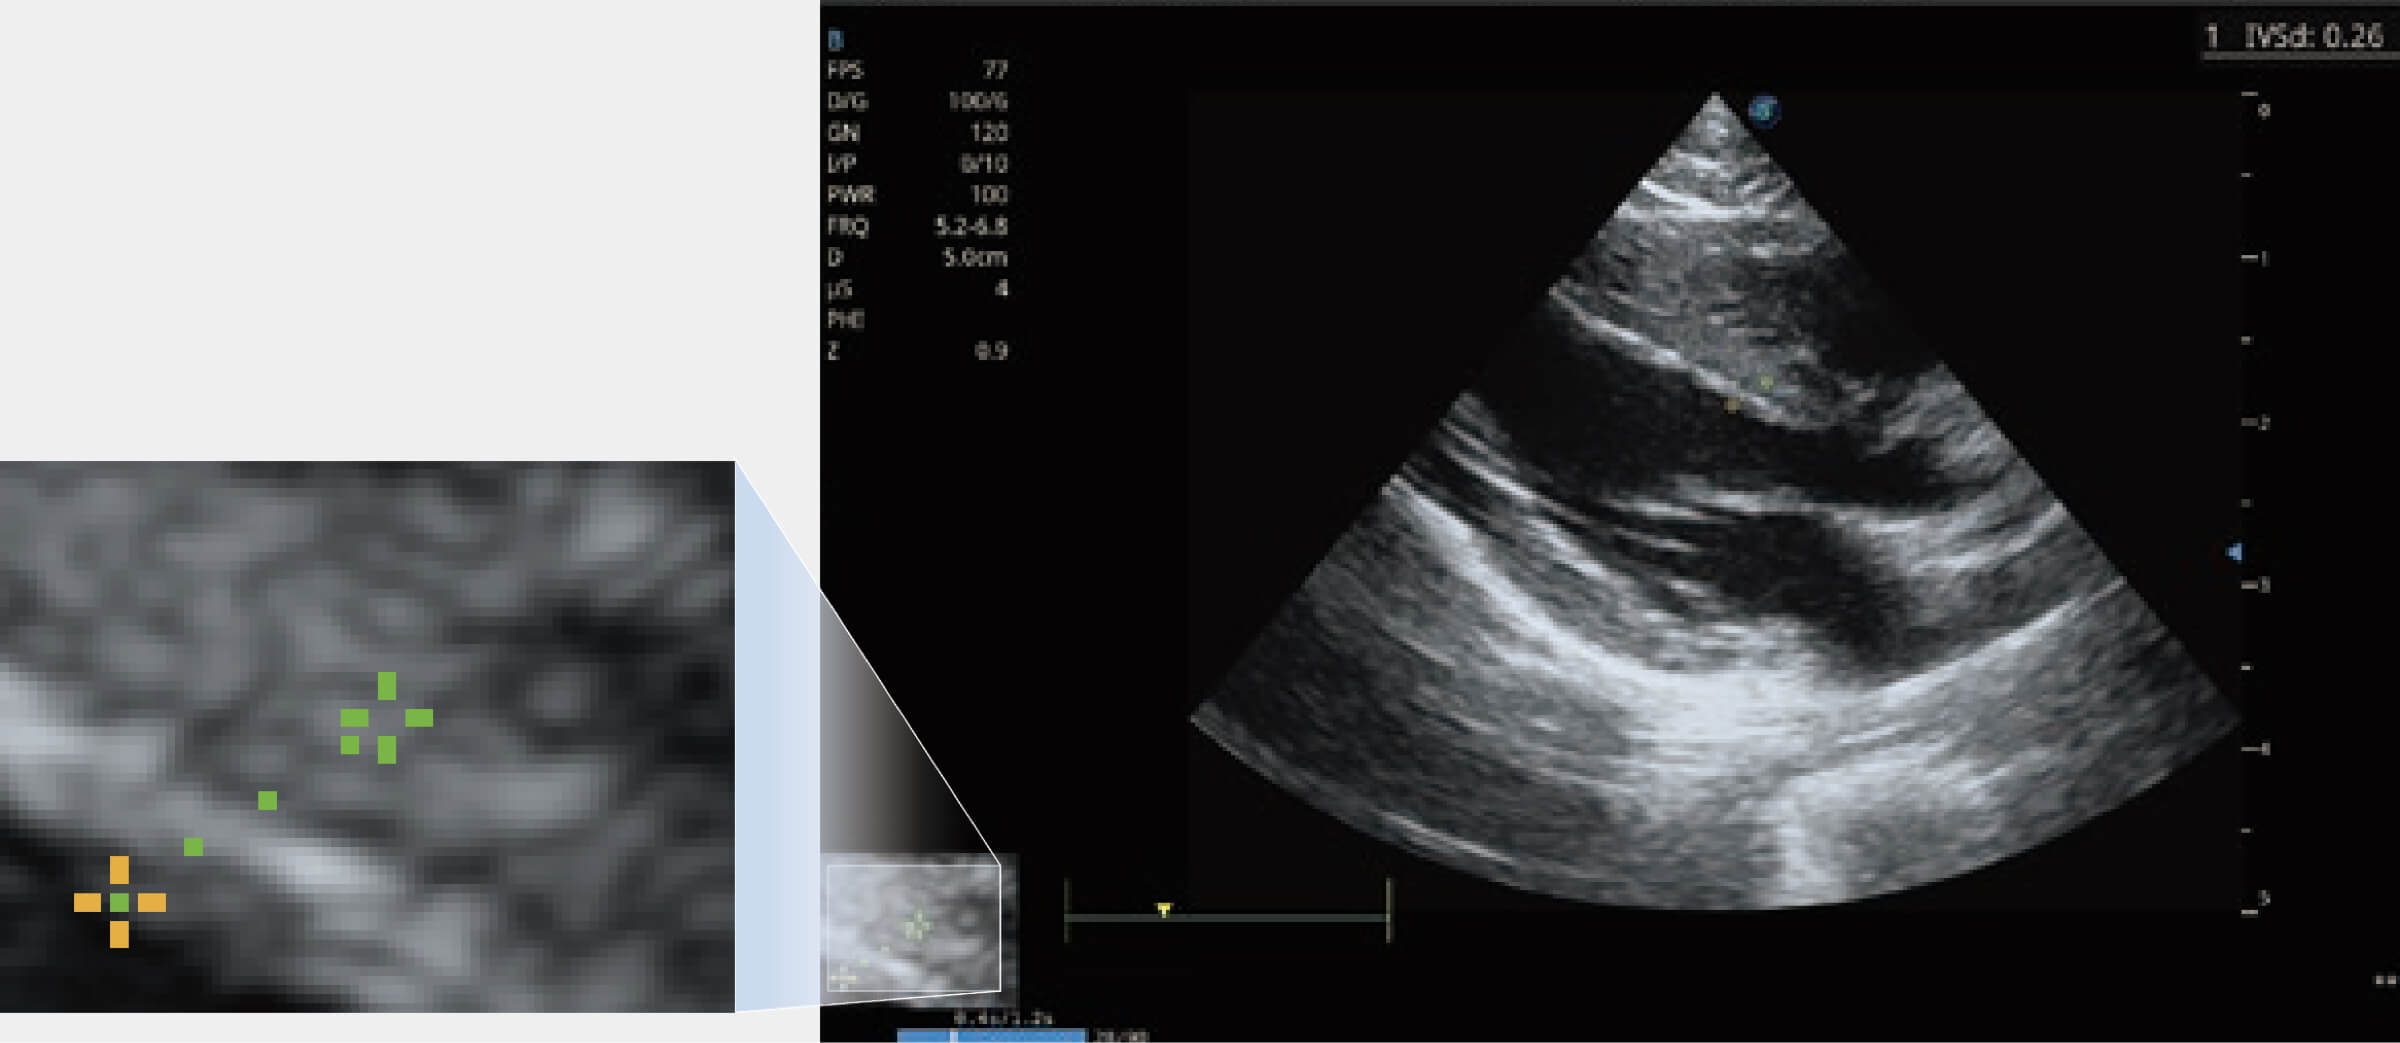

通过心肌识别技术与二维斑点追踪技术相结合,对心脏的超声图像进行量化分析。计算心肌17个节段的应变、应变率、速度、位移等,并通过牛眼图的形式进行呈现。

能够基于左心室壁追踪和辛普森法,自动计算射血分数,支持多个可移动点描迹,与手动测量相比,极大节省了动物医生的时间和精力。